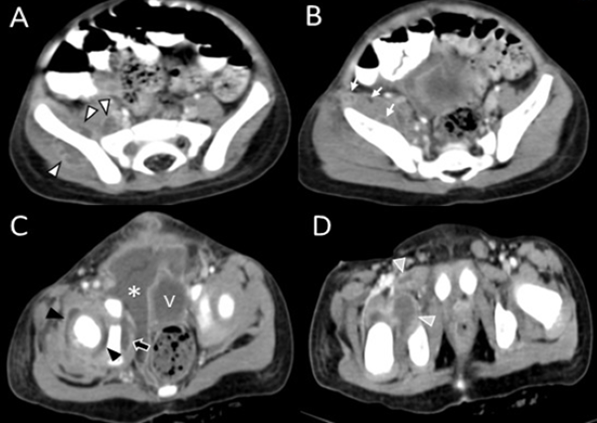

El servicio de ortopedia decide manejo quirúrgico por sospecha de artritis séptica mediante artrotomía evacuadora con reducción abierta de luxación de cadera. El cultivo de líquido serohemático extraído de la cápsula articular no reportó crecimiento. Como exámenes de control se le realizó al paciente una TC de abdomen simple y contrastado donde se evidencia la presencia de múltiples lesiones con contenido líquido en su interior y realce periférico al medio de contraste en varias regiones musculares como iliopsoas, glúteo medio, obturador externo, obturador interno y pectíneo. Adicionalmente se observa gran colección intrapélvica que desplaza lateralmente la vejiga y la presencia de líquido periarticular en cadera derecha, hallazgos radiológicos consistentes con piomiositis multifocal con afectación de cadera derecha (fig. 2). Al ser valorado por cirugía pediátrica en conjunto con ortopedia deciden optar por un manejo conservador por ambas partes y continúan tratamiento antibiótico. Obteniéndose completa resolución de los abscesos como se evidencia en la resonancia magnética realizada días después, sin embargo, persiste subluxación de cadera derecha, derrame articular, edema del musculo glúteo mayor y edema óseo en articulación sacroilíaca derecha consistente sacroileitis de origen infeccioso (fig.3)

Figura 2. Tomografía de abdomen y pelvis con contraste en cortes axiales que demuestra (A) Absceso de músculo psoas, ilíaco y de glúteo medio (puntas de flecha blanca). (B) Aumento de volumen y múltiples abscesos del músculo iliopsoas (flechas blancas). (C) Absceso en músculo obturador interno (flecha negra), colección intrapélvica (asterisco blanco) que desplaza la vejiga lateralmente (V) y líquido periarticular en cadera derecha (puntas de flecha negra). (D) Abscesos en músculos obturador externo y pectíneo (puntas de flecha gris)